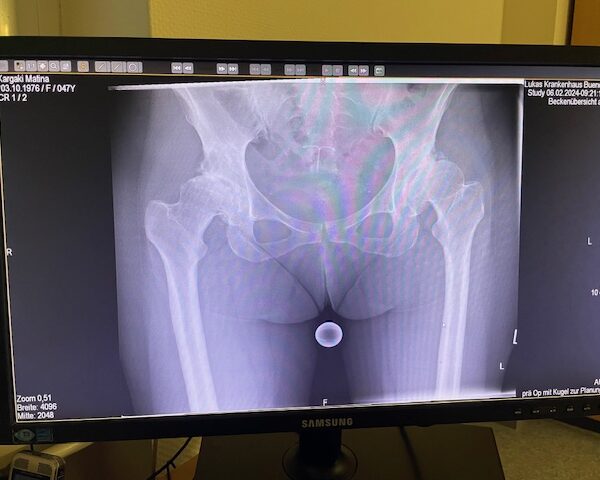

Η ασθενής είχε απευθυνθεί από χρόνια σε πολλούς συναδέλφους ορθοπεδικούς στην Ελλάδα και το εξωτερικό. Είχε προηγηθεί ήδη διεξοδικός απεικονιστικός έλεγχος (ακτινογραφίες λεκάνης και ισχίου, αξονική και μαγνητική τομογραφία).

Το 2024 όταν πλέον η ασθενής απευθύνθηκε σε εμένα, ακολούθησε εκ νέου ακτινογραφικός έλεγχος ώστε να μπορέσει να πραγματοποιηθεί ο προεγχειρητικός ψηφιακός σχεδιασμός του Χειρουργείου.

Ο ακτινογραφικός έλεγχος έδειχνε προχωρημένες εκφυλιστικές αλλοιώσεις και αλλοίωση της ανατομίας της κοτύλης και του μηριαίου.